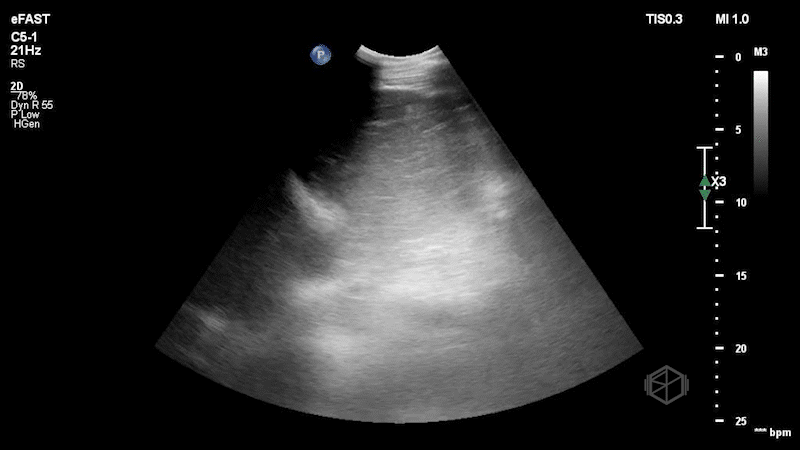

Left upper quadrant ultrasound demonstrating a hiatal hernia with stomach herniating through.

The stomach is swirling with food contents and is visible on both sides of the diaphragm.